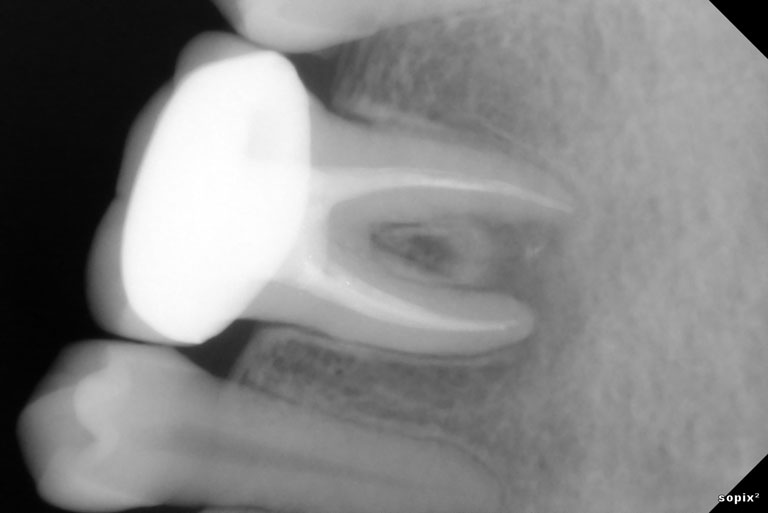

Root Canal Treatment Solution

Untuk setiap kondisi masalah gigi kamu, selalu ada solusi terbaik.

Penanganan yang tepat dengan alat dan teknologi yang memadai menjadikan hasil yang optimal